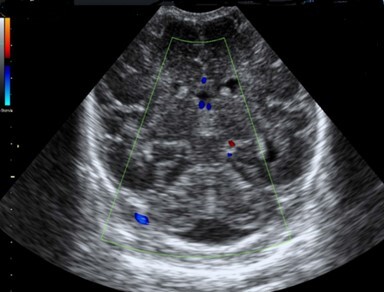

Neonatology Wide Magna Cisterna 2 Image